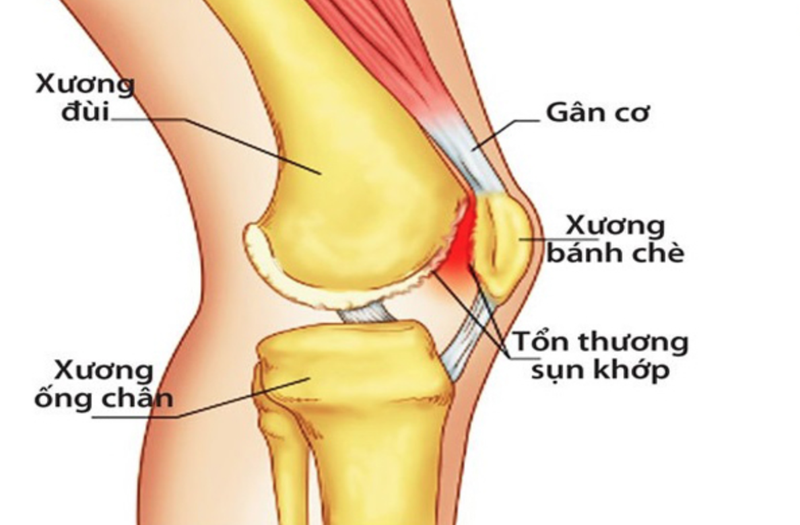

Xương bánh chè là một phần xương nhỏ ở đầu gối, cụ thể là trước khớp gối và trước đầu dưới của xương đùi.

Đây là một xương vừng lớn nhất trên cơ thể, nằm trong hệ thống duỗi của đầu gối, che chở mặt trước khớp gối.

Xương bánh chè được cấu tạo bên ngoài là xương đặc, bên trong là xương xốp, tạo nên tổ chức có hình tam giác. Xươnxg gồm có 2 mặt, 2 bờ, 1 đỉnh và 1 đáy.

- Mặt xương: Mặt trước hơi lồi ra và có nhiều khía rãnh, nhằm cho gân cơ tứ đầu đùi bám vào. Mặt sau 4/5 là diện khớp. Chúng tiếp khớp với diện bánh chè của xương đùi.

- Bờ xương: có 2 bờ là trong và ngoài.

- Nền: đây là phần để gân cơ tứ đầu đùi bám vào.

- Đỉnh: ở bên dưới, có dây chằng bánh chè bám vào.

Do nằm trong hệ thống duỗi đầu gối nên xương bánh chè có chức năng che chở mặt trước khớp gối. Chúng giữ chức năng chính trong hệ thống duỗi gối do đó phần xương này rất dễ bị tổn thương do tai nạn giao thông, lao động hoặc là sinh hoạt.